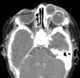

Dacryocystitis

Dacryocystitis is an infection of the lacrimal sac, secondary to obstruction of the nasolacrimal duct at the junction of lacrimal sac. The term derives from the Greek dákryon (tear), cysta (sac), and -itis (inflammation). [Source: Wikipedia ]